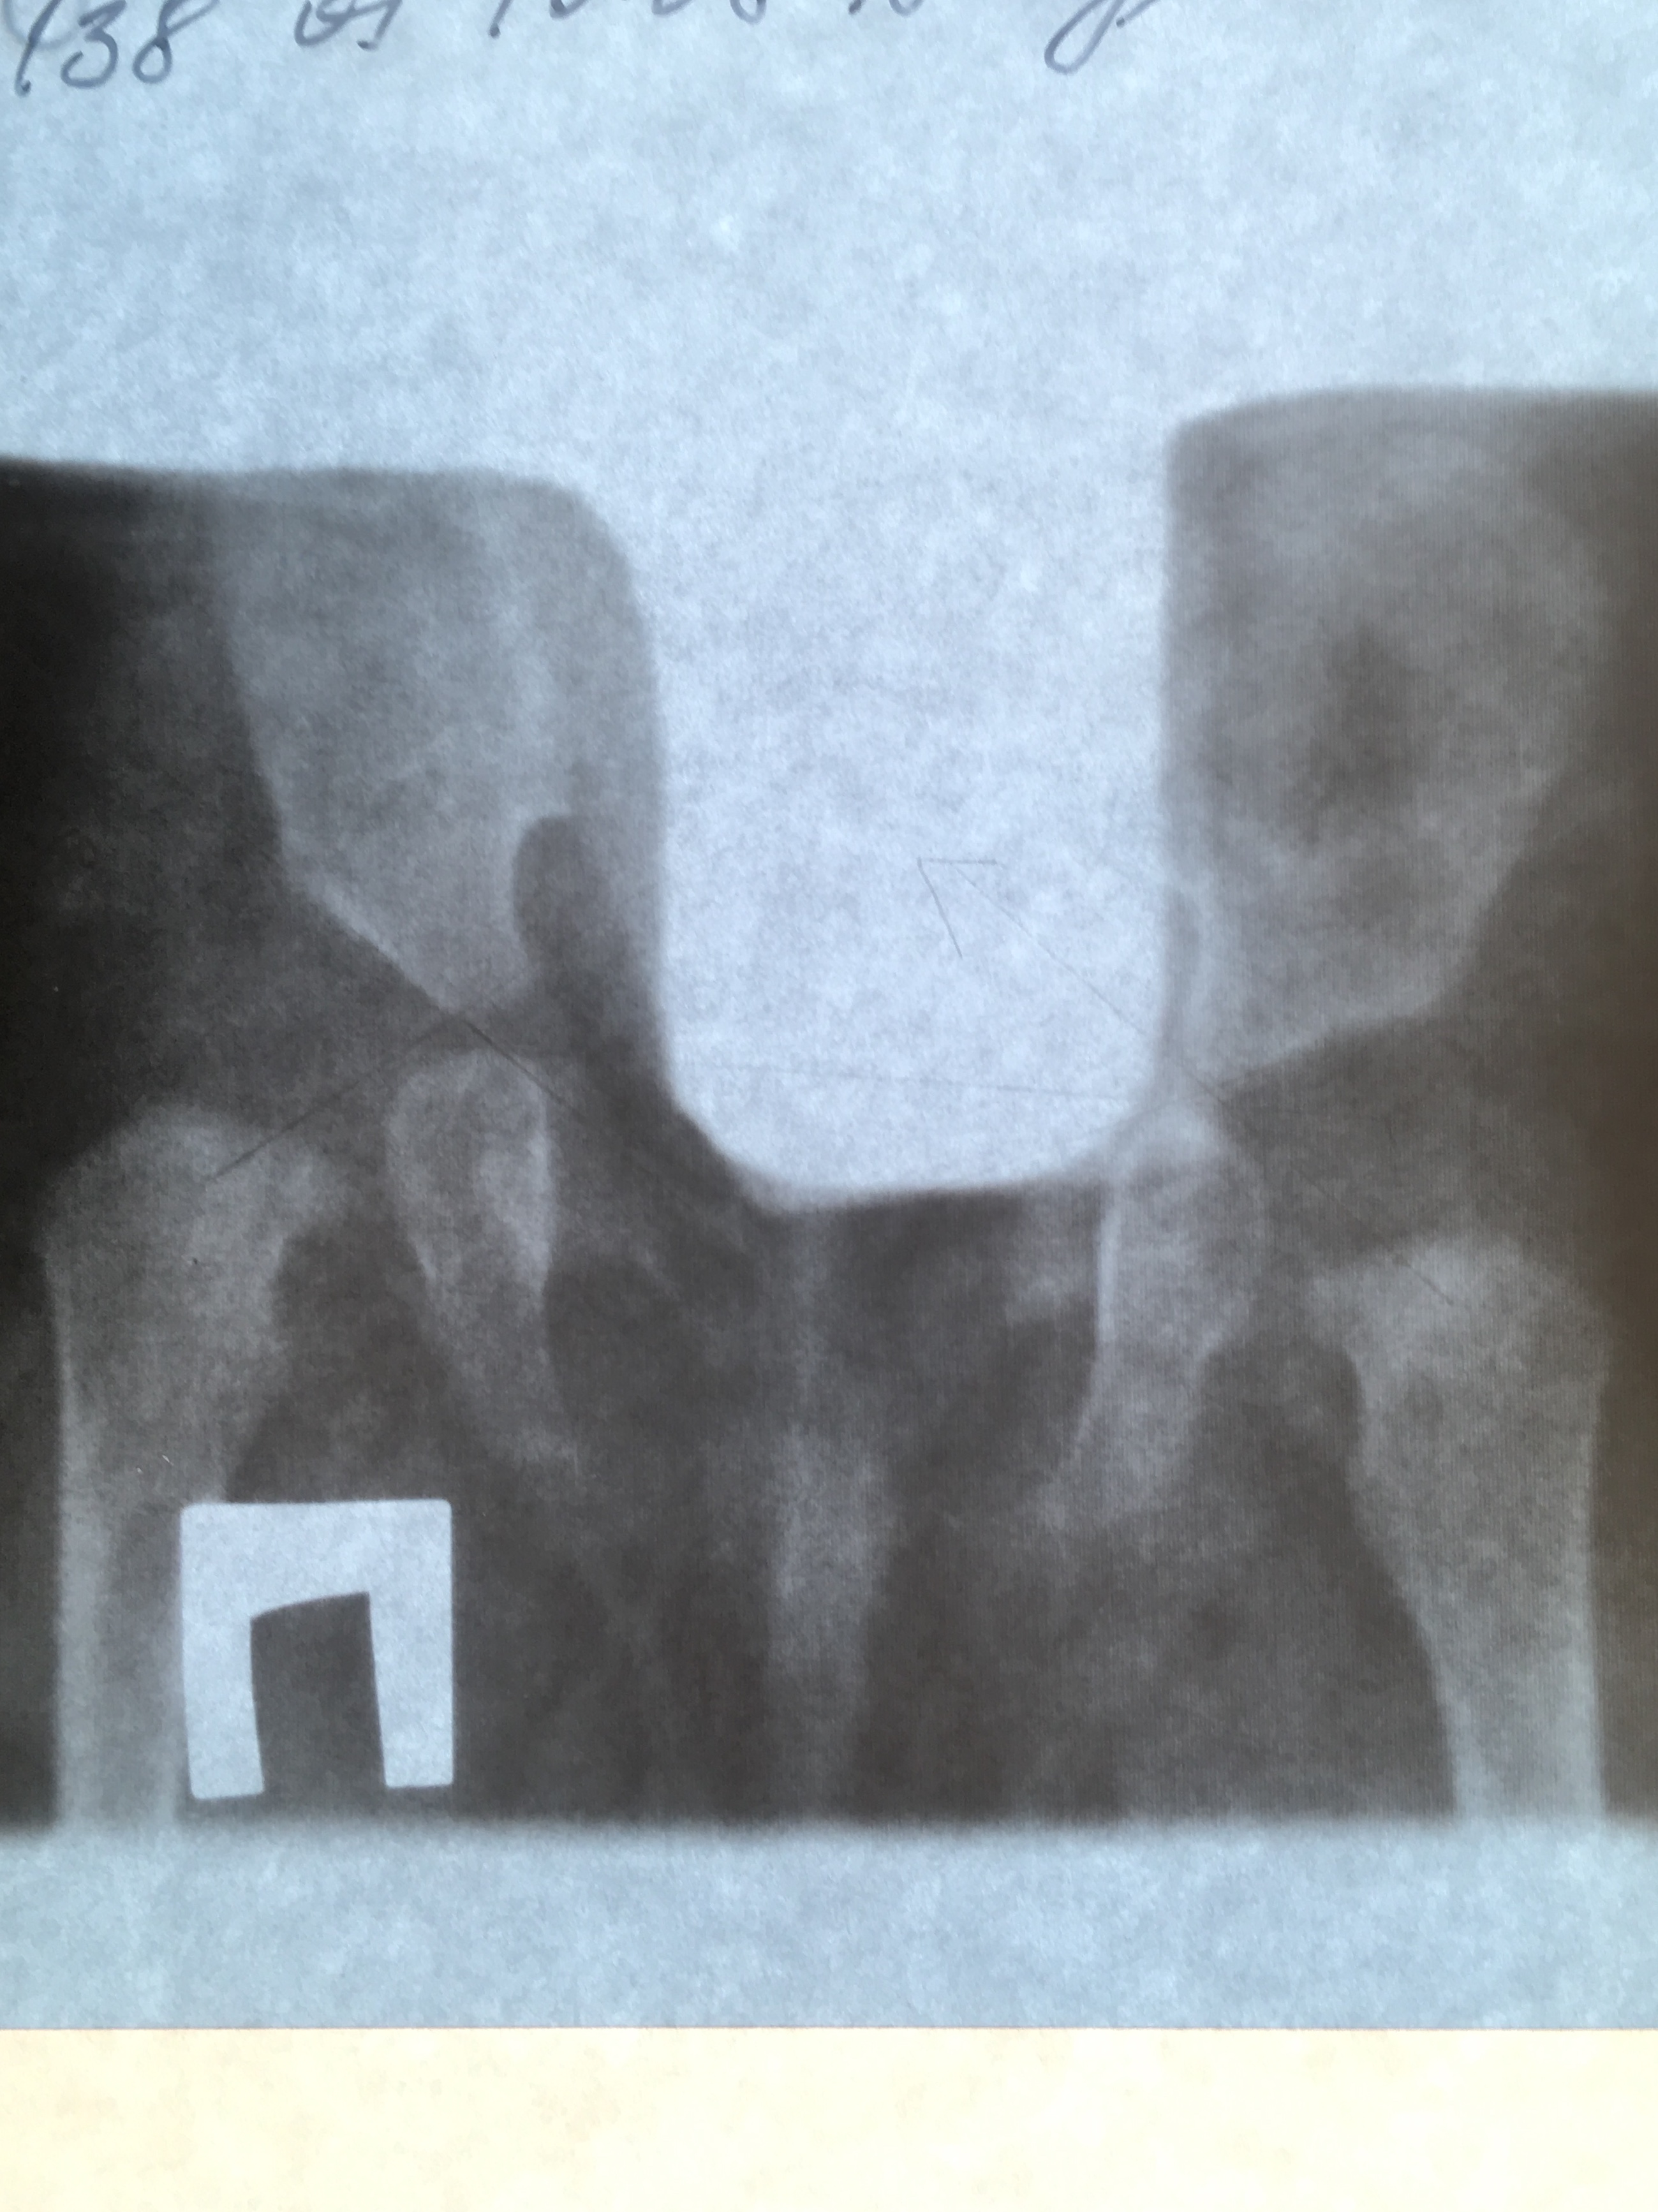

ребенку в 3 мес поставили ДЗ дисплазия справа. Первый снимок ацеб. Индекс справа 40, слева 30. Головка справа децентрирована

2 снимок спустя 3 мес ношения стремян , прохождения процедур . Справа опять 40 гр, слева 25, головки центрированы

спустя месяц: справа 35,продольные оси шеек на медиальный край вертлюжной впадины  .слева 25, на У образный хрящ

опять написано о не симметричной укладке. Скажите правильно ли сделано заключение ? Один ортопед сказал что по таким неровным снимкам судить нельзя . Так ли это? И на последнем снимке опять децентрация ?

Ну, что сказать, у ребенка был врожденный вывих правого бедра. Вы лечитесь, ситуация выправляется. Но считаю, что и справа и слева имеется децентрация шеек бедренных костей, оси направлены на средние трети крыш вертлужных впадин.

Андрей Юрьевич, это по последнему 3 снимку ? А то что снимки не ровные не влияет на углы ? Мне один орторентгенометрия говорил про какие-то параллели , что они не параллельны по снимкам, и поэтому нельзя судить о правильном  измерении. Просто по УЗИ все центрировано ,и скос крыши не такой большой. А тут все не так уж и радужно получается, и на 3 снимке угол 35,нам 8 мес это же тот же почти вывих что и был в 3 мес. Получается ?